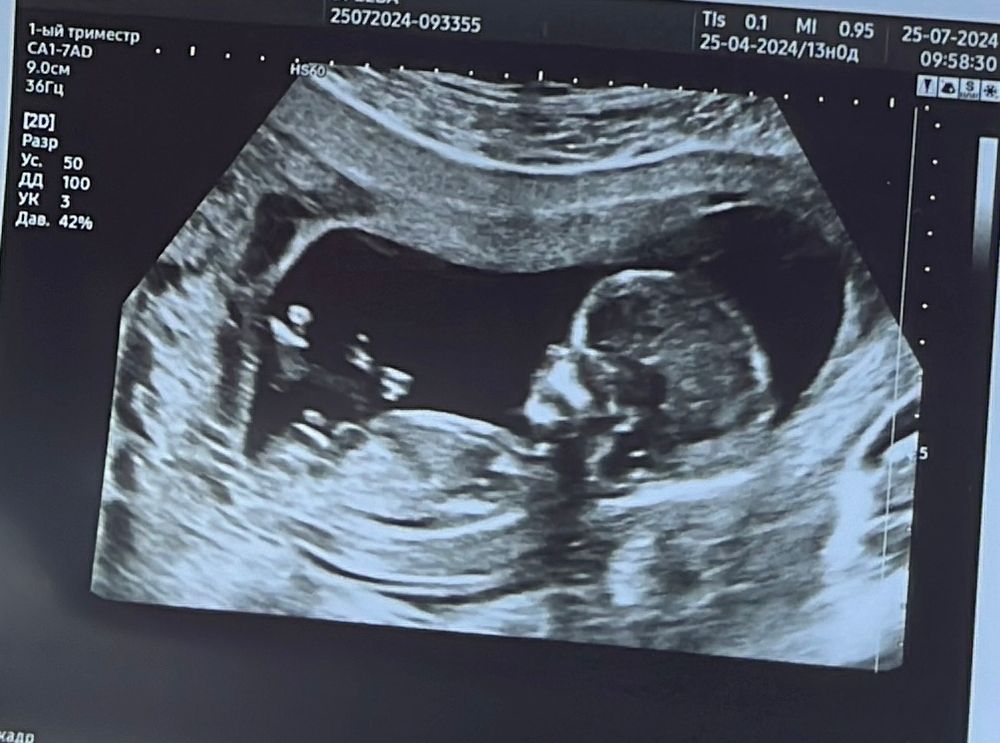

Katiii в Благополучная беременность год Как вам кажется девочка или мальчик? Анализы, скрининги Первый сынок ,очень хочется девчонку 😇 Посмотрите еще 20 записей на эту тему Лучший ответ Ника Девочка 🌸 25.07.2024 Ответить Отменить Ответить Дарья Девочка 25.07.2024 Ответить Katiii Как вы это видите ?₽) 25.07.2024 Ответить Леди баг Katiii, половой бугорок торчит прямо) так что, с большОй вероятностью, девочка. Был бы он задран вверх, то это говорит о мальчике. 25.07.2024 Ответить Елена Паршина Леди баг, а у нас как думаете? Или не понятно 25.07.2024 Ответить Леди баг Елена Паршина, не видать положение бугорка, как раз ножка закрыла, так что 50/50😄 25.07.2024 Ответить Замена клион д! Повышенный риск по Т21 РБ Чаты Беременных Выберите чат: Январята-2026 Февралята-2026 Мартята-2026 Апрелята-2026 Майчата-2026 Июнята-2026 Июлята-2026 Августята-2026